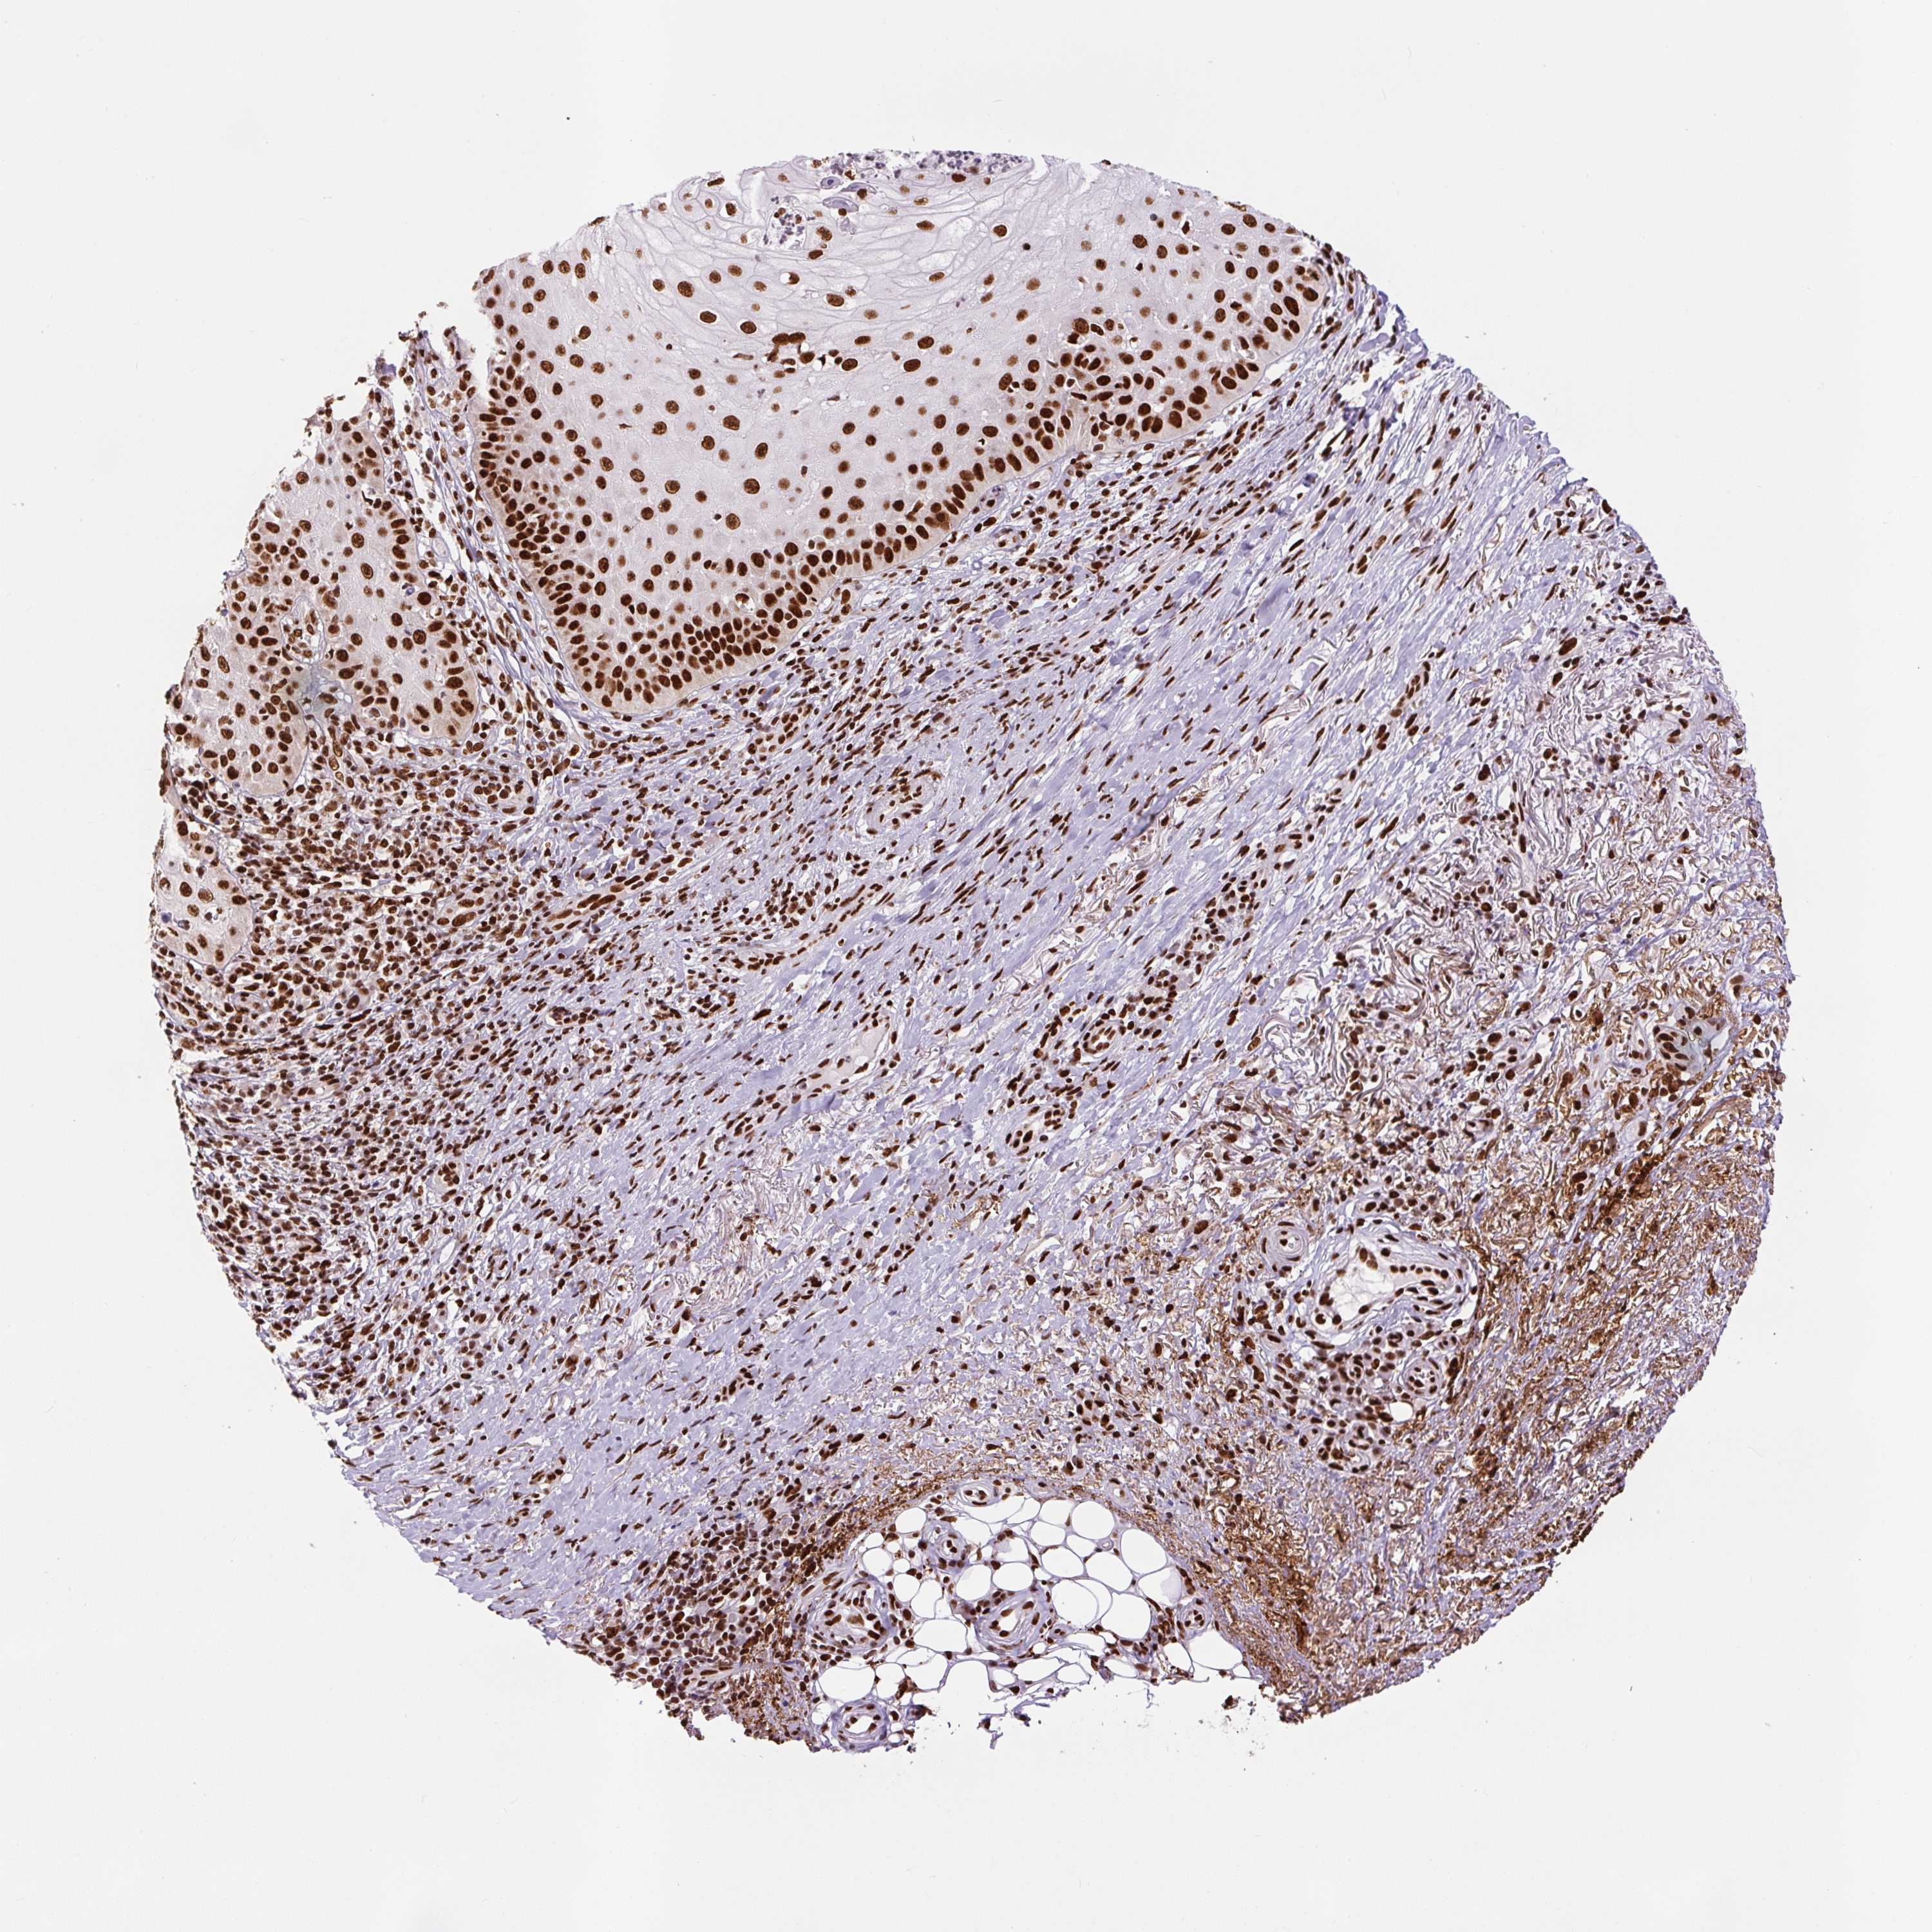

SKIN CANCER - Protein expressioni

A mouse-over function shows sample information and annotation data. Click on an image to view it in a full screen mode. Samples can be filtered based on level of antibody staining by selecting one or several of the following categories: high, medium, low and not detected. The assay and annotation is described here.

Antibody stainingi

Antibody staining in the annotated cell types in the current human tissue is reported as not detected, low, medium, or high, based on conventional immunohistochemistry profiling in selected tissues. This score is based on the combination of the staining intensity and fraction of stained cells.

Each image is clickable and will lead to virtual microscopy that enables deeper exploration of all samples and also displays staining intensity scores, fraction scores and subcellular localization as well as patient and tissue information for each sample.

Antibody HPA008784

Antibody CAB033036

Antibody CAB058691

Squamous cell carcinoma, NOS

Squamous cell carcinoma, metastatic, NOS

Basal cell carcinoma

Papilloma, NOS